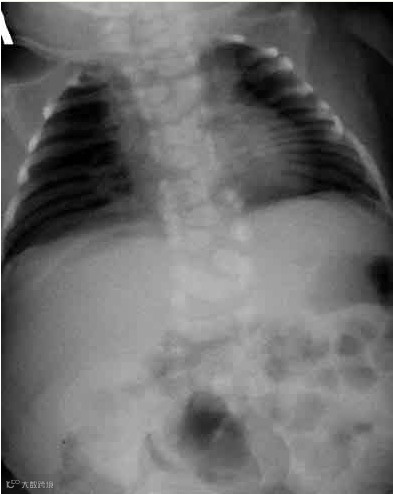

已有文献报道DMRT2基因的纯合突变导致严重的肋骨畸形(缺失,融合和发育不良的肋骨),椎骨畸形(椎板椎间融合和椎体不规则骨化)以及轻度脊柱侧弯。患儿出生时存在严重的呼吸功能不全。DMRT2基因敲除的小鼠也表现出严重的肋骨和椎骨缺损。目前尚未被OMIM数据库收录。

严重的肋骨畸形,椎体的不规则骨化